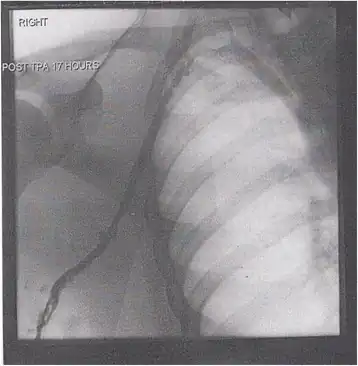

Thrombolysis is the injection of an enzyme into the veins to dissolve blood clots, and while this treatment has been proven effective against the life-threatening emergency clots of stroke and heart attacks, randomized controlled trials[139][140][141] have not established a net benefit in those with acute proximal DVT.[5][142] Drawbacks of catheter-directed thrombolysis (the preferred method of administering the clot-busting enzyme[5]) include a risk of bleeding, complexity,[l] and the cost of the procedure.[125] Although, while anticoagulation is the preferred treatment for DVT,[125] thrombolysis is a treatment option for those with the severe DVT form of phlegmasia cerula dorens (bottom left image) and in some younger patients with DVT affecting the iliac and common femoral veins.[12] Of note, a variety of contraindications to thrombolysis exist.[125] In 2020, NICE kept their 2012 recommendations that catheter-directed thrombolysis should be considered in those with iliofemoral DVT who have "symptoms lasting less than 14 days, good functional status, a life expectancy of 1 year or more, and a low risk of bleeding."[138]

A mechanical thrombectomy device can remove DVT clots, particularly in acute iliofemoral DVT (DVT of the major veins in the pelvis), but there is limited data on its efficacy. It is usually combined with thrombolysis, and sometimes, temporary IVC filters are placed to protect against PE during the procedure.[143] Catheter-directed thrombolysis with thrombectomy[141] against iliofemoral DVT has been associated with a reduction in the severity of post-thrombotic syndrome at an estimated cost-effectiveness ratio of about $138,000[m] per gained QALY.[144][145] Phlegmasia cerulea dolens might be treated with catheter-directed thrombolysis and/or thrombectomy.[19][143]

In DVT in the arm, the first (topmost) rib can be surgically removed as part of the typical treatment when the DVT is due to thoracic outlet syndrome or Paget–Schroetter syndrome. This treatment involves initial anticoagulation followed by thrombolysis of the subclavian vein and staged first rib resection to relieve the thoracic outlet compression and prevent recurrent DVT.[146]

A venogram before catheter-directed thrombolysis for Paget–Schroetter syndrome, a rare and severe arm DVT shown here in a judo practitioner, with highly restricted blood flow shown in the vein -

After treatment with catheter-directed thrombolysis, blood flow in the axillary and subclavian vein was significantly improved. Afterwards, a first rib resection allowed decompression. This reduces the risk of recurrent DVT and other sequelae from thoracic outlet compression.[147]